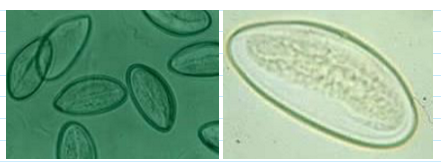

enterobius vermicularis eggs

30 x 50 um ; embryonated

Thin, smooth, transparent shell

Oval and asymmetrical with one side flattened (looks like deflated football)

Usually contain a well-developed larvae

trichuris trichiura eggs

54 x 22 um

Distinct barrel shape

Refractile, convex, hyaline polar plugs at both ends

Unembryonated internal mass

capillaria philippinensis eggs

Must not confuse with Trichuris eggs

35-45 x 20-25 um

More squarish than Trichuris eggs

Less conspicuous polar plugs

Flatter and less prominent

Thick striated shell